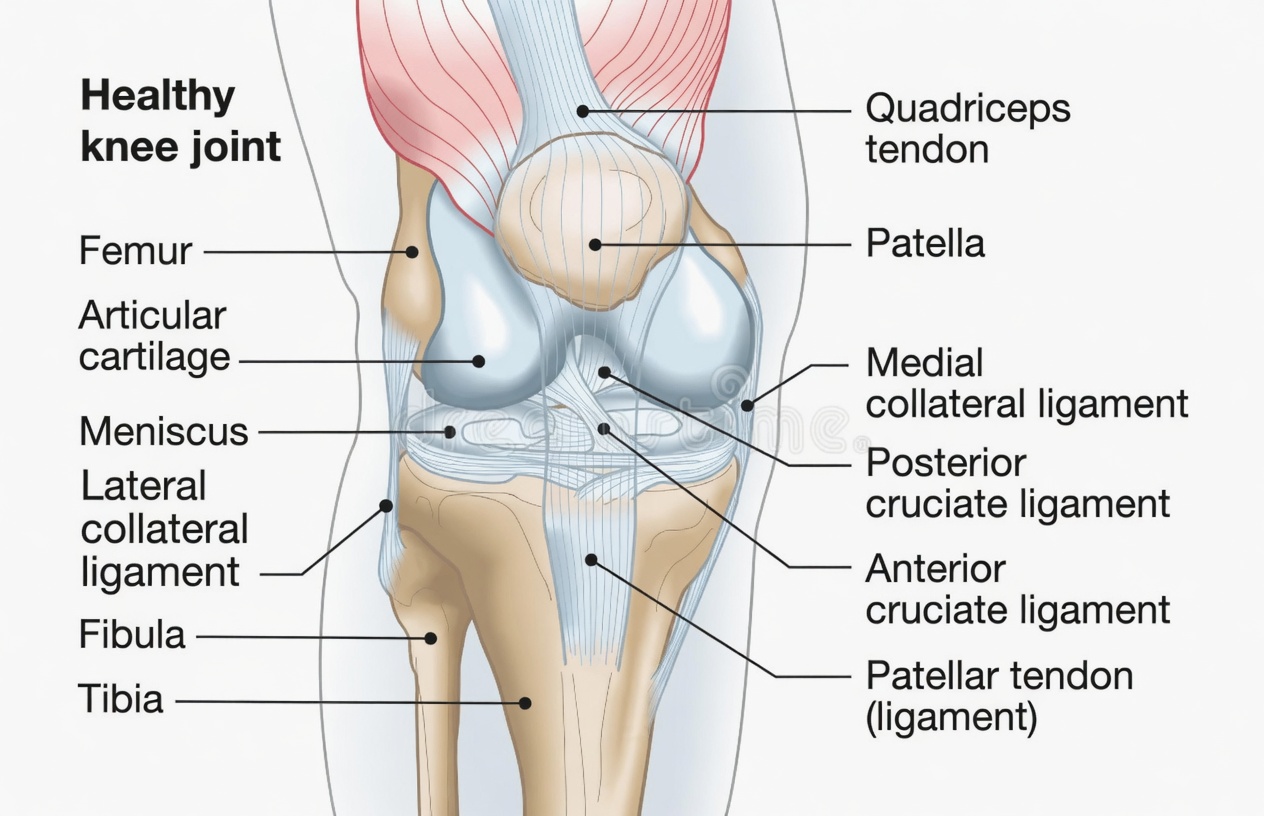

Understanding Knee Cartilage and Why Knees Hurt So Often

Knee cartilage works like a built-in shock absorber between bones. It helps joints glide smoothly, reducing friction every time you stand, walk, or take the stairs. Over time, cartilage can wear down. When that cushioning thins, bones rub more, inflammation rises, and knee pain becomes harder to ignore.

Many adults experience ongoing knee discomfort that can worsen with inactivity and impact overall quality of life. While cartilage wear may seem inevitable, diet can influence inflammation and joint function. Because salmon is rich in joint-supporting nutrients, it’s often discussed in research focused on inflammation and cartilage integrity.